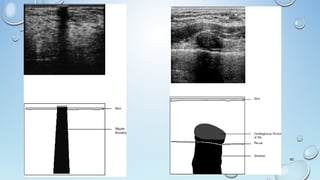

Lymph Node

• Solid nodule

• Ovoid

• Echogenic fatty hilum

• The Subcutaneous Fat LayerSubcutaneous Fat Layer Is Demonstrated Superficially As

Hypoechoic Tissue Compared To The Glandular Tissue From Which It Is

Separated By A Well-defined Scalloped Margin.

• Normal DuctsDucts Are Often Visible, Particularly In The Subareolar Region,

As Anechoic Tubular Structures.

• Deep To The Glandular Tissue, A Retromammary Fat LayerA Retromammary Fat Layer Is Usually

Visible And, Behind This, The Structures Of The Chest WallChest Wall.